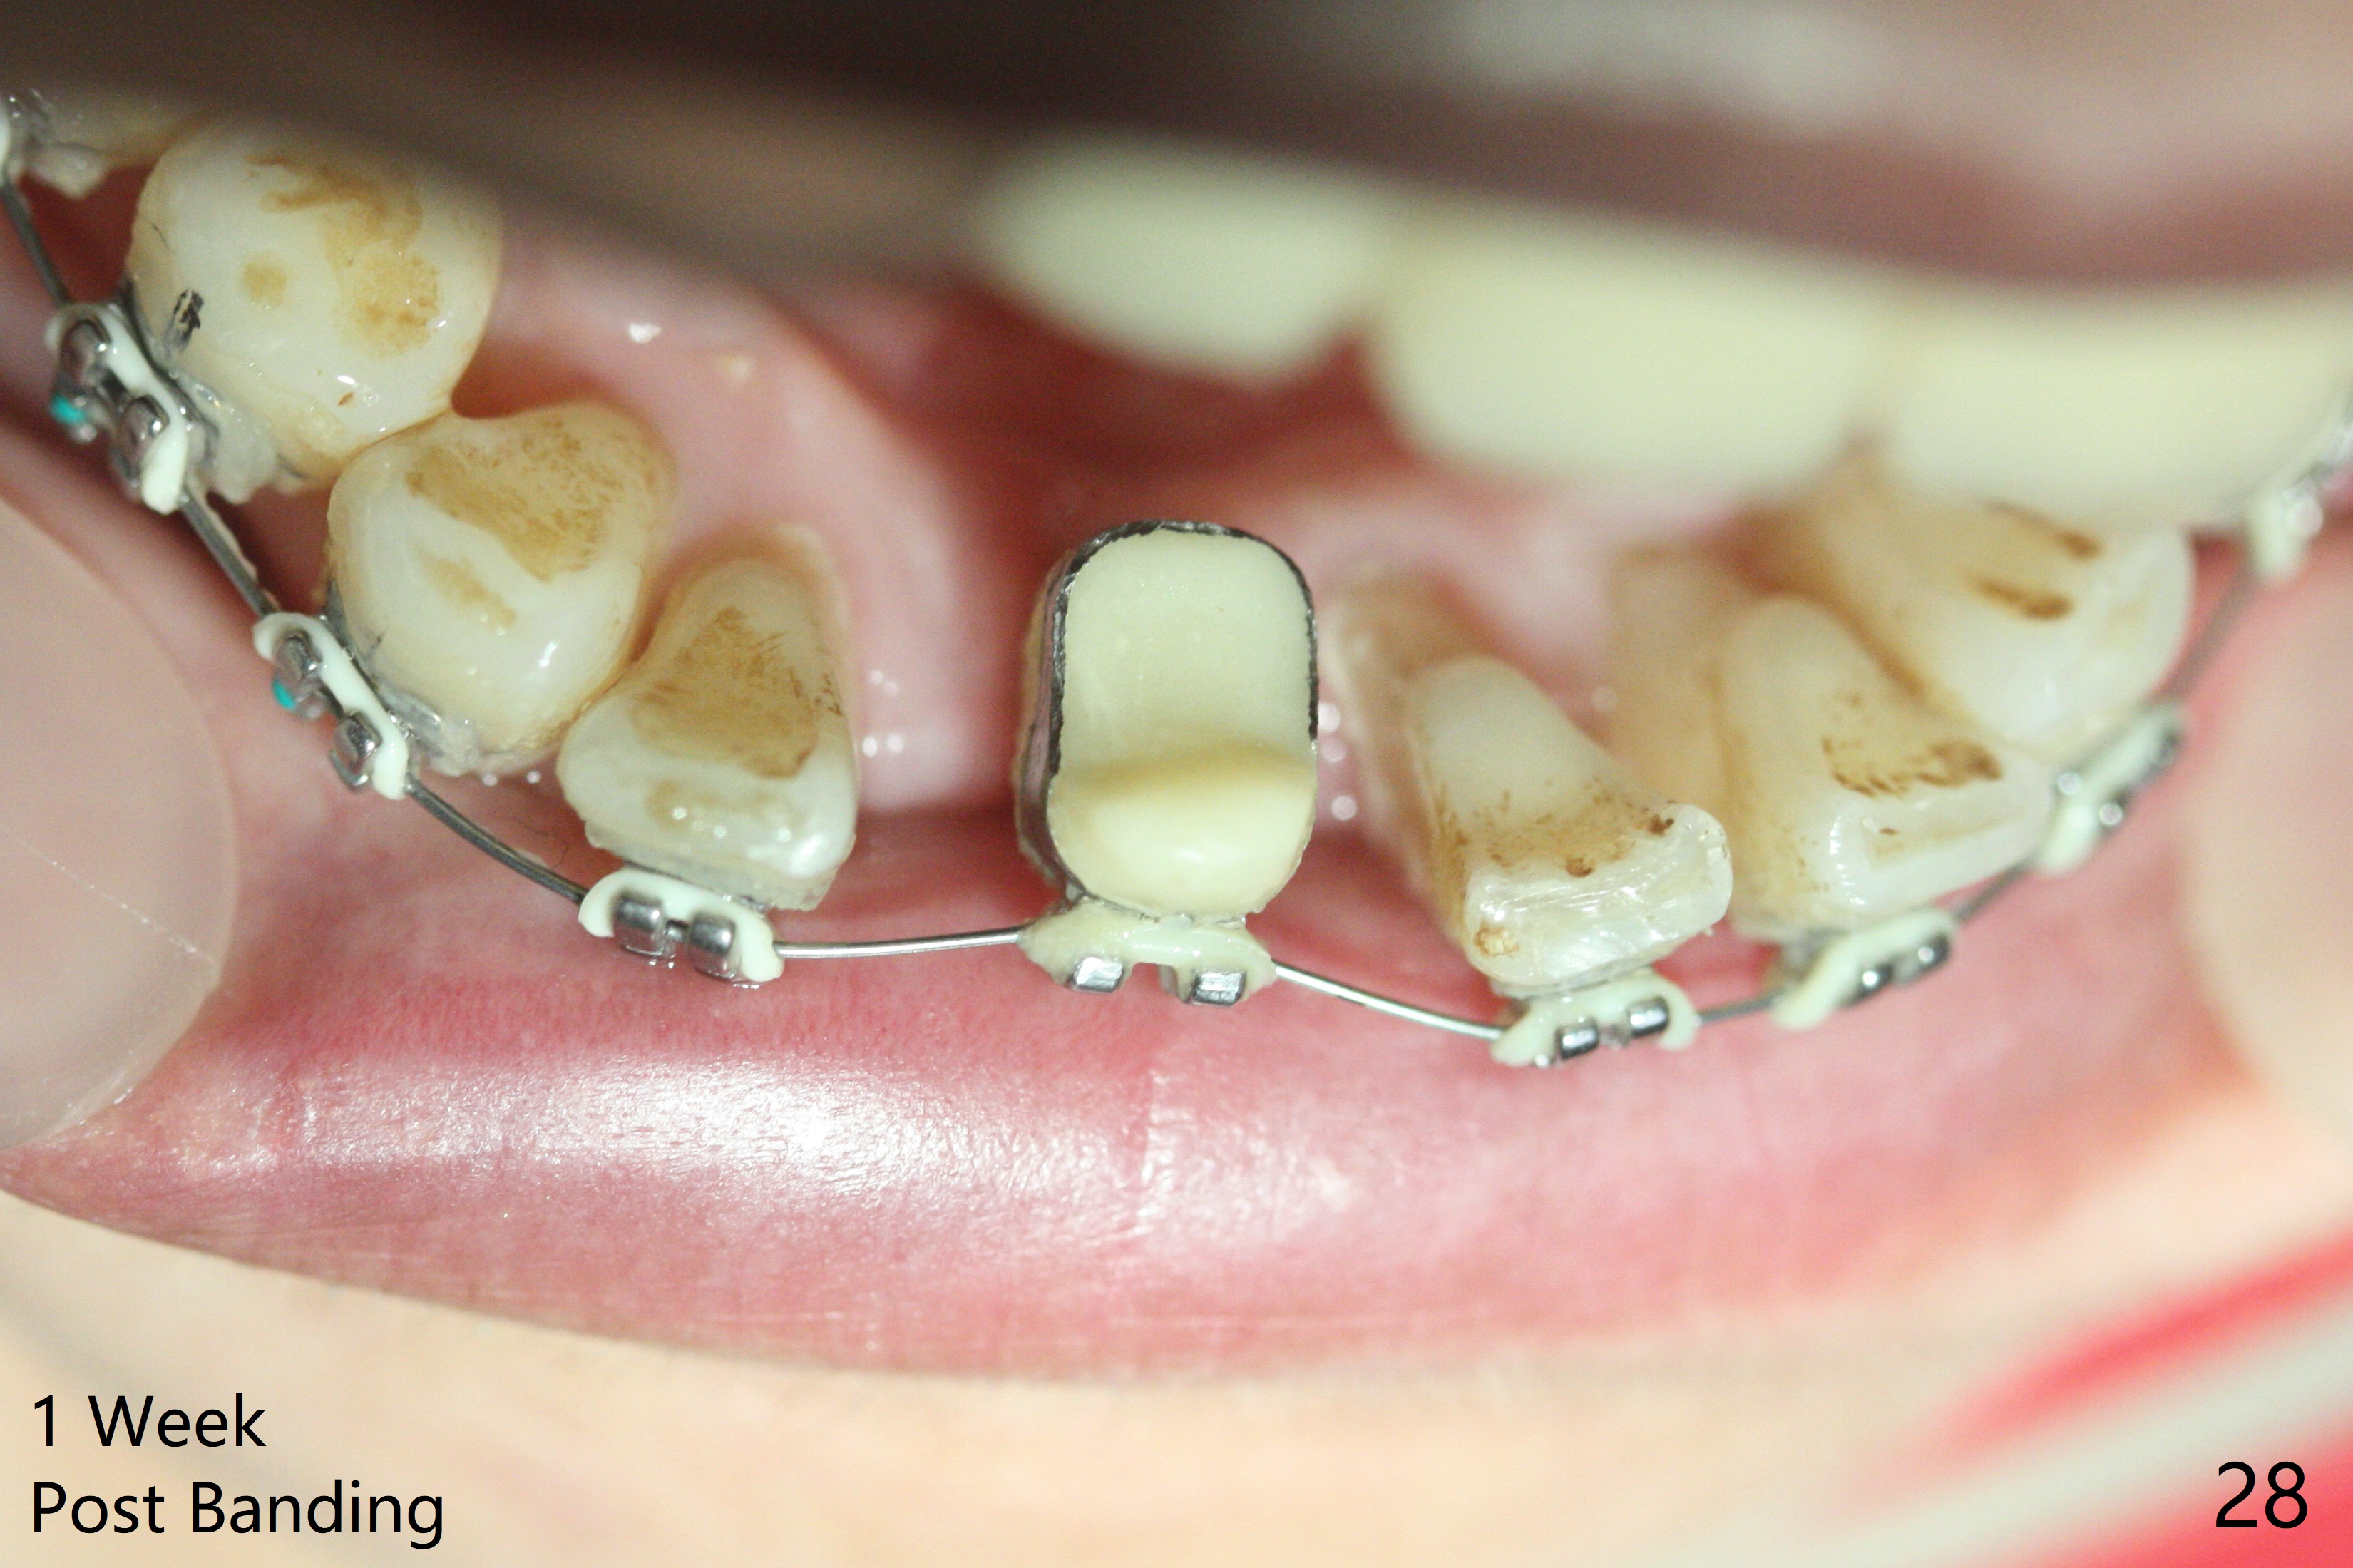

56岁女十分恐惧治疗,缺失右下1,其余切牙由于骨质吸收颊侧移位(图一:1,2),但是她不愿意拔除,同意右下1种植,牙周骨手术,植骨;植体整合后作为支抗,矫正移位下门牙。为了防止忘记舌侧瓣分离,先做舌侧切口(图二),然后颊侧瓣松弛分离(图三),包括使用前牙隧道刀(图四)切断颊侧骨膜,松弛到颊侧瓣能向舌侧牵拉3-4毫米(图五),舌侧瓣骨膜下广泛,深部分离(好像不能切断骨膜,图六),放置导板,磨平狭窄的牙槽嵴(图七:O(osteotomy)),植入2.5x12(4)毫米一段式植体(图八:故意舌侧植入,以便以后矫正),在颊侧骨板打多个出血洞(图八:箭头),然后把在平的器皿上形成的粘性骨板(sticky bone,图九),放置于植体和移位切牙周围(图十),接着使用消毒过的橡皮障punch(图十一(纸头相当于PRF膜;事先给助手示范))在三个PRF膜(图十二)打洞,套在植体和门牙上(图十三: 箭头),防止膜(图十四)和骨块(图十五,十六:*)移位,最后还必须使用最原始方法牙周敷料保护伤口(图十七)。术后9天,舌侧牙周敷料脱落,伤口稍微裂开(图十八)。术后18天撤除敷料,伤口裂开处有新鲜肉芽组织生长(图十九(*:下面是填入的骨粉,将是增宽的牙槽嵴(如果你是乐观主义者)),二十)。病人十分感激我们帮助她度过难关。她的确有sleep apnea,否定tongue thrust。术后三个月植体周围没有明显骨质吸收(图二十一至二十三),左下1,2轻度反合(图二十四),植体周围软组织健康(图二十五),5-5安置矫正器(图二十六,二十七,12 niti)。一周后下切牙向舌侧移动(图二十八),左下1,2反合纠正(图二十九)。再一周变化不大(图三十),植牙圈有些松动,两周后将重做临时牙冠,槽往舌侧移动。结果病人提前回来,植牙槽舌侧移位。一周后右下2不适(图三十一),尝试近中牵引(图三十二)。